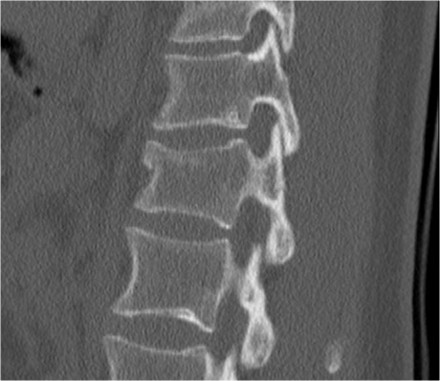

Here's another example.

You could call these compression fractures.

There is loss of height with a dense band of impaction and there is an anterosuperior corner fracture on both levels.

But look at the spinous processes.

One of the spinous processes is in two pieces and the two pieces are widely separated.

So this is a distraction fracture, also known as Chance fracture.

Now when you describe such a fracture the first word in your report should be distraction, i.e. morphology: 4 points.